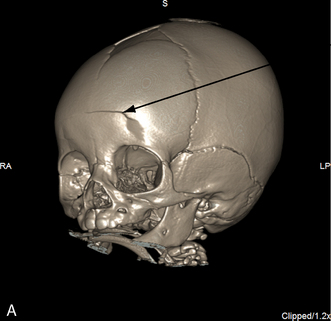

Skull Fractures

A skull fracture is a break in the continuity of the cranial bones that may or may not be associated with displacement of the bone fragments. Skull fractures are present in approximately one fourth of all patients hospitalized with head injury and can be further classified as simple (closed injury) or compound (open injury). Compound fractures are frequently associated with dural tears; these increase the risk of abscess formation and meningitis.78 The fracture itself may be benign, but is often associated with injury to the underlying meninges or vasculature.

Approximately three fourths of all skull fractures in children are simple or linear skull fractures. In this form of skull fracture, the bone fragments remain approximated and the dura mater is not penetrated.

A depressed skull fracture is present when one or more bone fragments are indented below the normal contour or table of the cranium. As a result, the skull is indented, and the brain tissue below the fracture is injured. A hematoma may cover the area of injury, and a cerebral contusion may be present below the fracture. The dura usually is not penetrated when a depressed skull fracture is present.

The clinical signs and symptoms associated with any skull fracture will depend on the location of the fracture and on the extent of the underlying cranial injury. Most skull fractures are diagnosed by radiographic examination rather than by clinical examination, because the vast majority of skull fractures are linear (i.e., the bone fragments remain approximated).

A basilar skull fracture is often not detectable on a radiograph, unless a blood-air level develops in the sphenoid sinus. A CT scan may be required to identify a basilar skull fracture. Approximately 40% of patients with EDH have no identified fractures.50

Depressed or compound skull fractures should be suspected whenever the contour of the patient's head is altered or whenever an obvious indentation in the skull is observed or palpated. If a depressed skull fracture is located over the sagittal or lateral sinus, profuse bleeding can develop from injury to these venous channels, and hypovolemic shock can result.